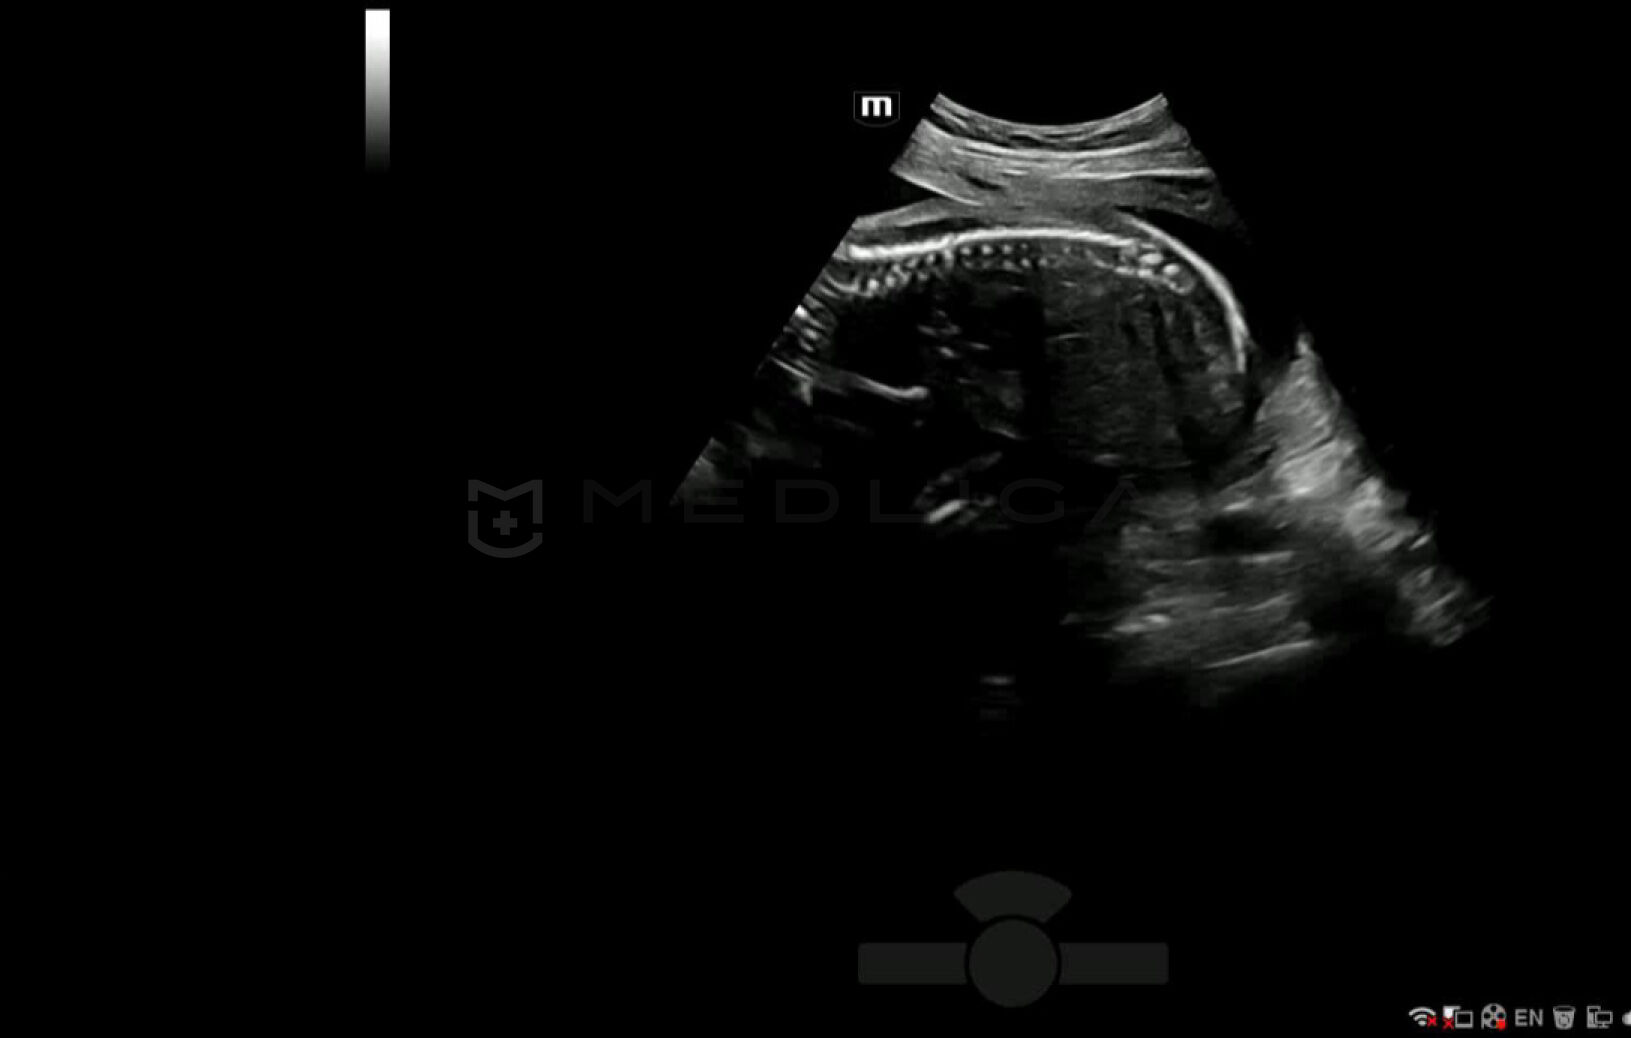

С легкостью получайте потрясающие 3D изображения позвоночника плода

- Автоматическое распознавание анатомии позвоночника плода

- Автоматическая подстройка зоны интереса и положения до оптимального

- Автоматический определение параметров рендеринга позвоночника

Место Smart Scene в технологии full-stack smartness